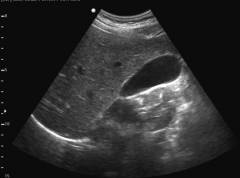

- Ультразвуковое исследование. Определяет положение, размеры и наличие камней в желчном пузыре.

- Ультразвуковое исследование. Метод позволяет оценить положение, размеры и толщину стенок желчного пузыря, а также наличие камней и аномалий.